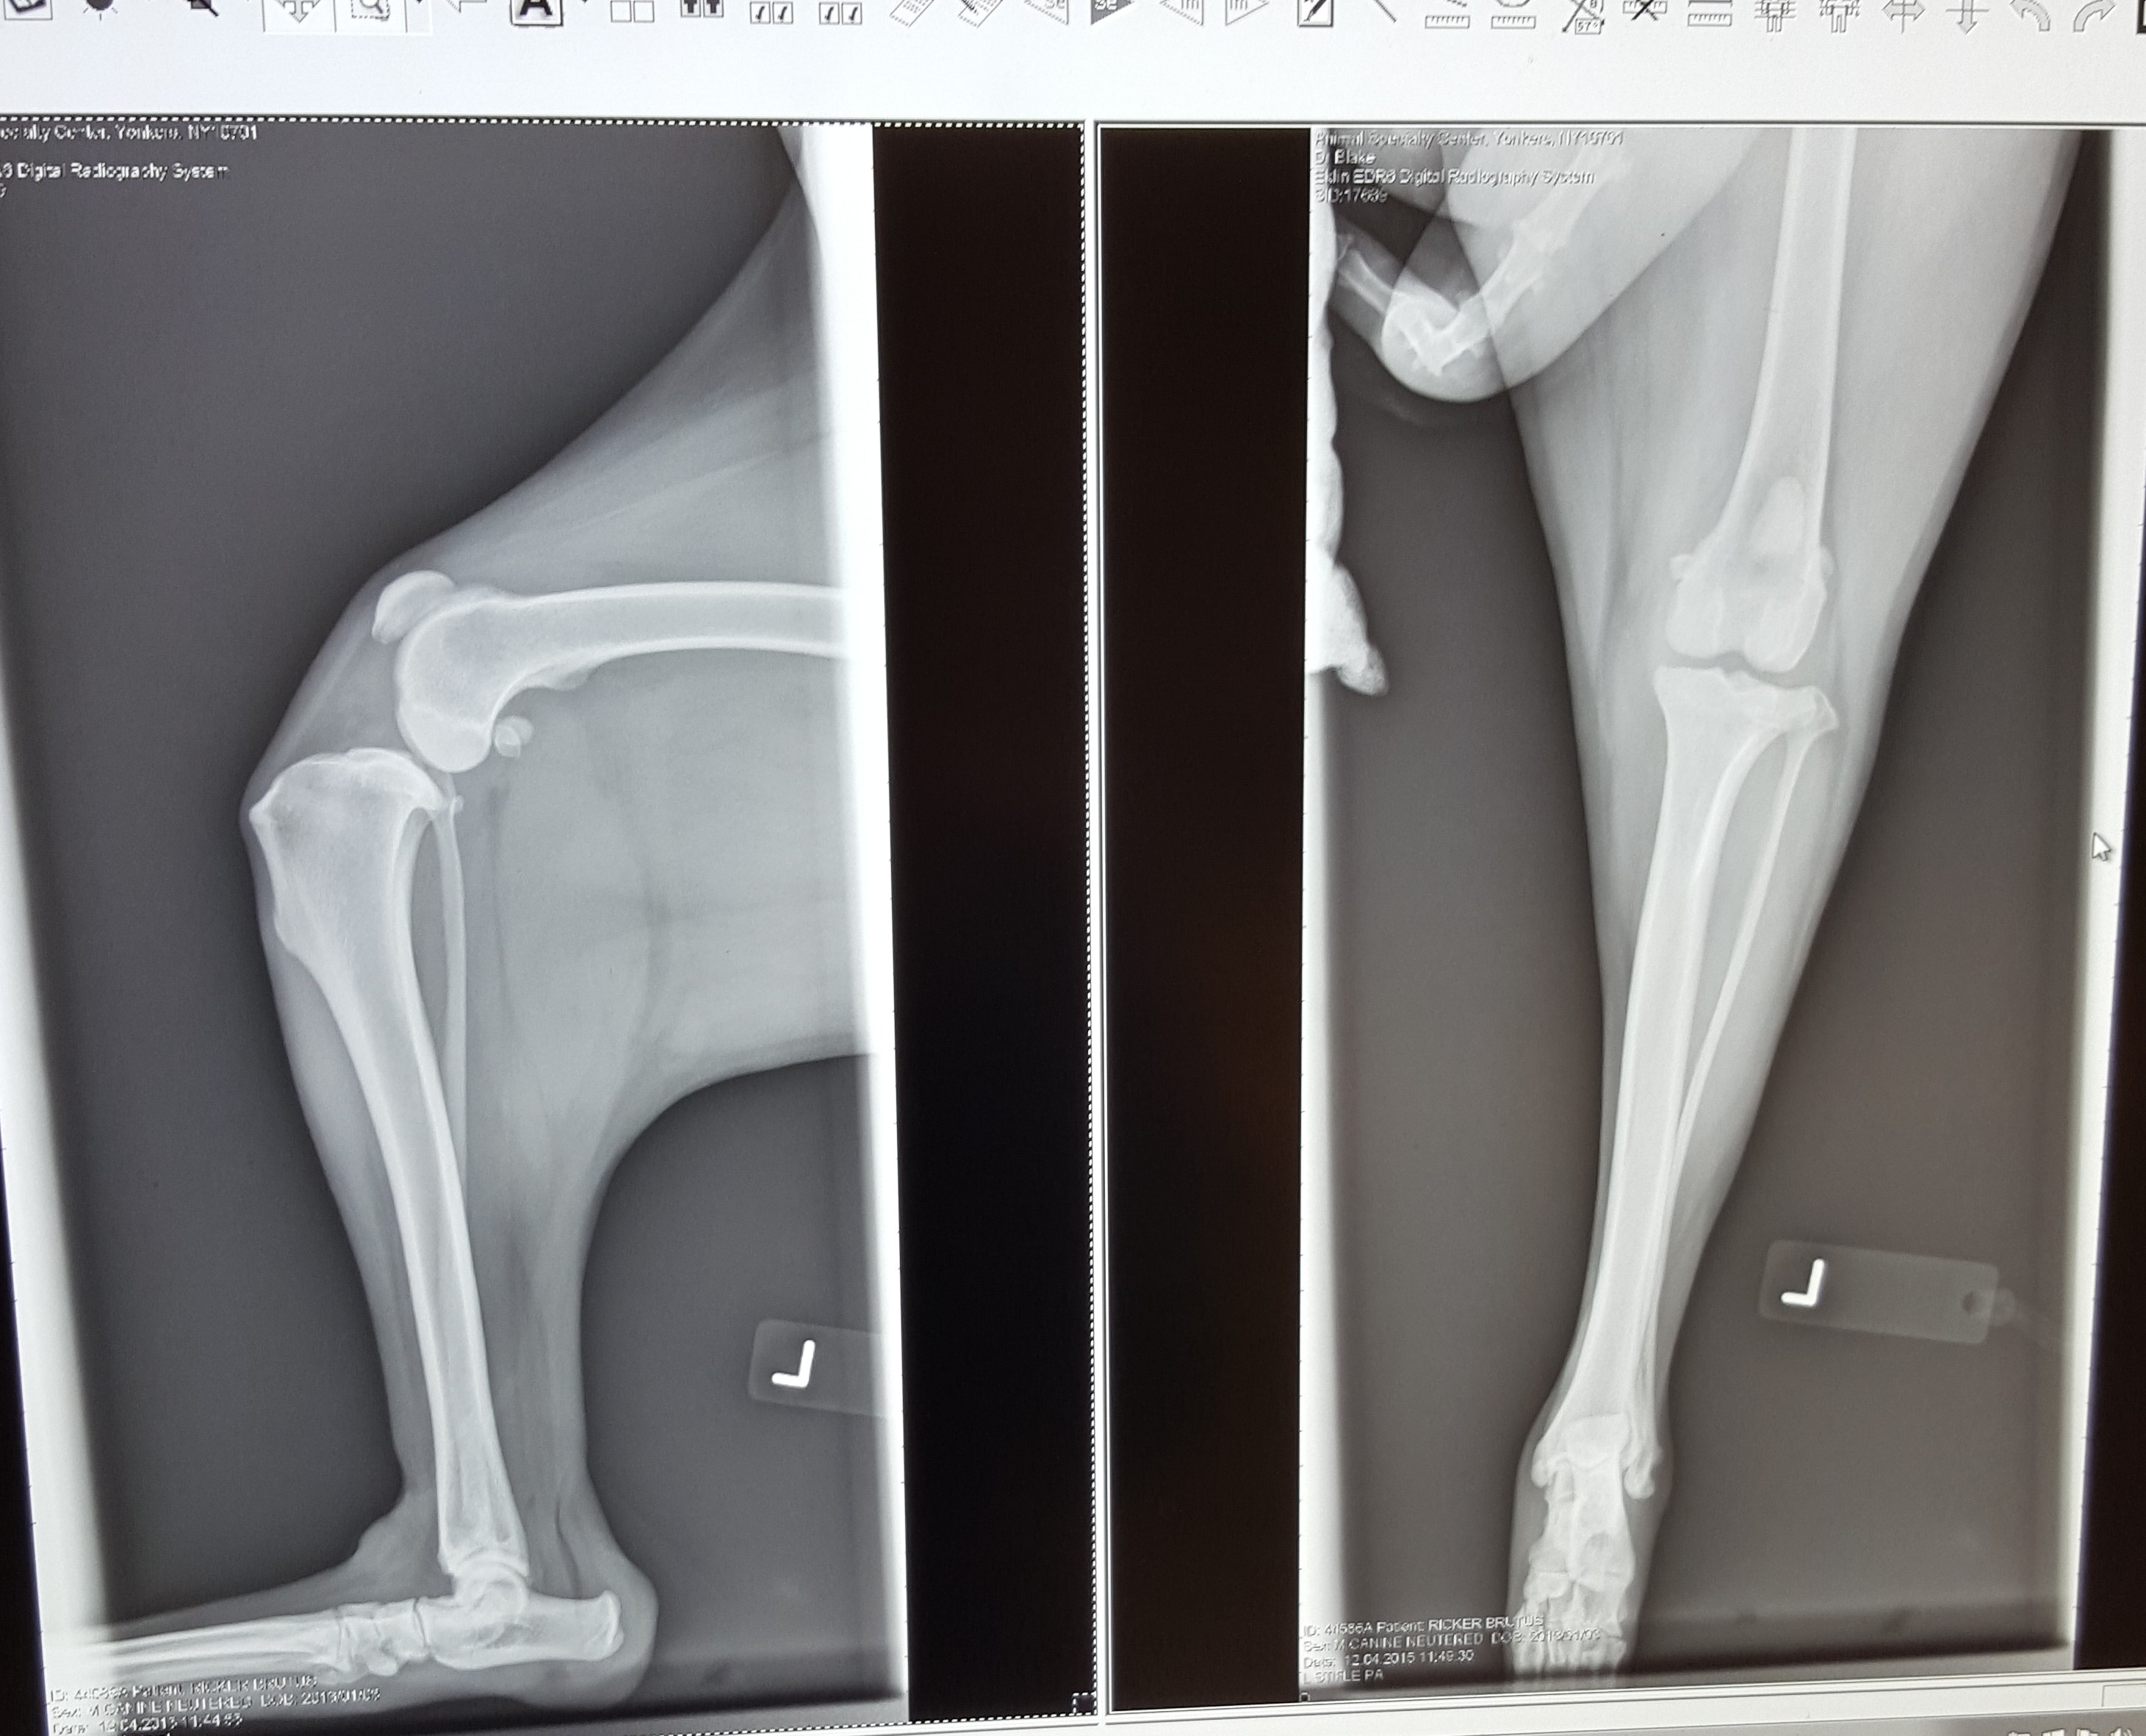

With TPLO surgery, the surgeon places a plate and screws into the bone after they have cut a curve in the tibia bone to reshaped it to allow for good movement and better stability. The CCL is removed because it can not be repaired and in some cases (like Brutus) the meniscus is found to be damaged and is also removed.

Here are pictures of Brutus’ knee showing before and after surgery. Pictures are taken just before surgery and then after the plate is in place, to compare and ensure proper placement before finishing up. The plate will be there for the rest of his life.